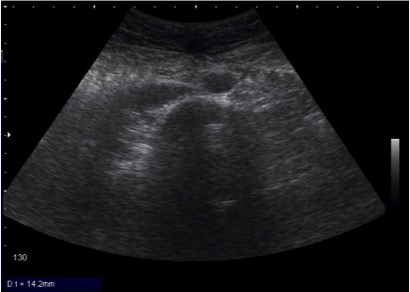

- Identify normal chest and abdominal anatomy

The RUQ should be divided into 3 zones.

1. Above/Below the diaphragm,

2. Morrison’s pouch (hepato-renal recess)

3. Para-colic gutter: Around the inferior hepatic edge/inferior pole of kidney

The key is to know your landmarks, and STOP, STAY and widely FAN through each zone well, adjusting your depth as necessary to keep the area of interest centered on your screen.

Start high to stay and fan (anterior to posterior) around the diaphragm. Then, SLIDE down into another rib space, stop, stay and fan around the entire kidney. An additional rib space may be necessary to evaluate the para-colic gutter.

Tips for RUQ Morrison’s Pouch (Hepato-Renal Recess) View:

If rib shadows get in the way, using the same trick above of patient inspiration can help. There are also a few false positive “traps” here.

First, the double line sign, seen around the kidney capsule as hyper-echoic double lines with hypo-echoic material in between, can be mistaken for free fluid. SEE ABSTRACT. However, free fluid will not be surrounded by hyperechoic lines and will not be in a contained structure.

Second, edge artifact from the liver/kidney interface occurs due to ultrasound physics and sound wave transmission between structures of different densities. It is seen as a dark thin line tracing off the edge of this interface extending to the bottom of the screen. . This differentiates it from free fluid, which will not extend past the liver.